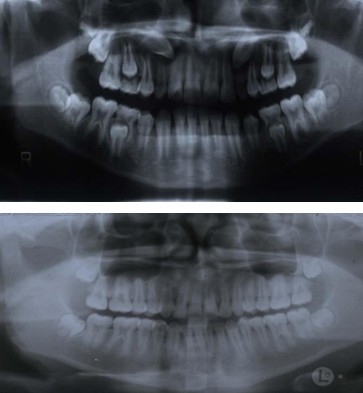

矫治前后全景片对照:

功能矫治前后全景片对照: